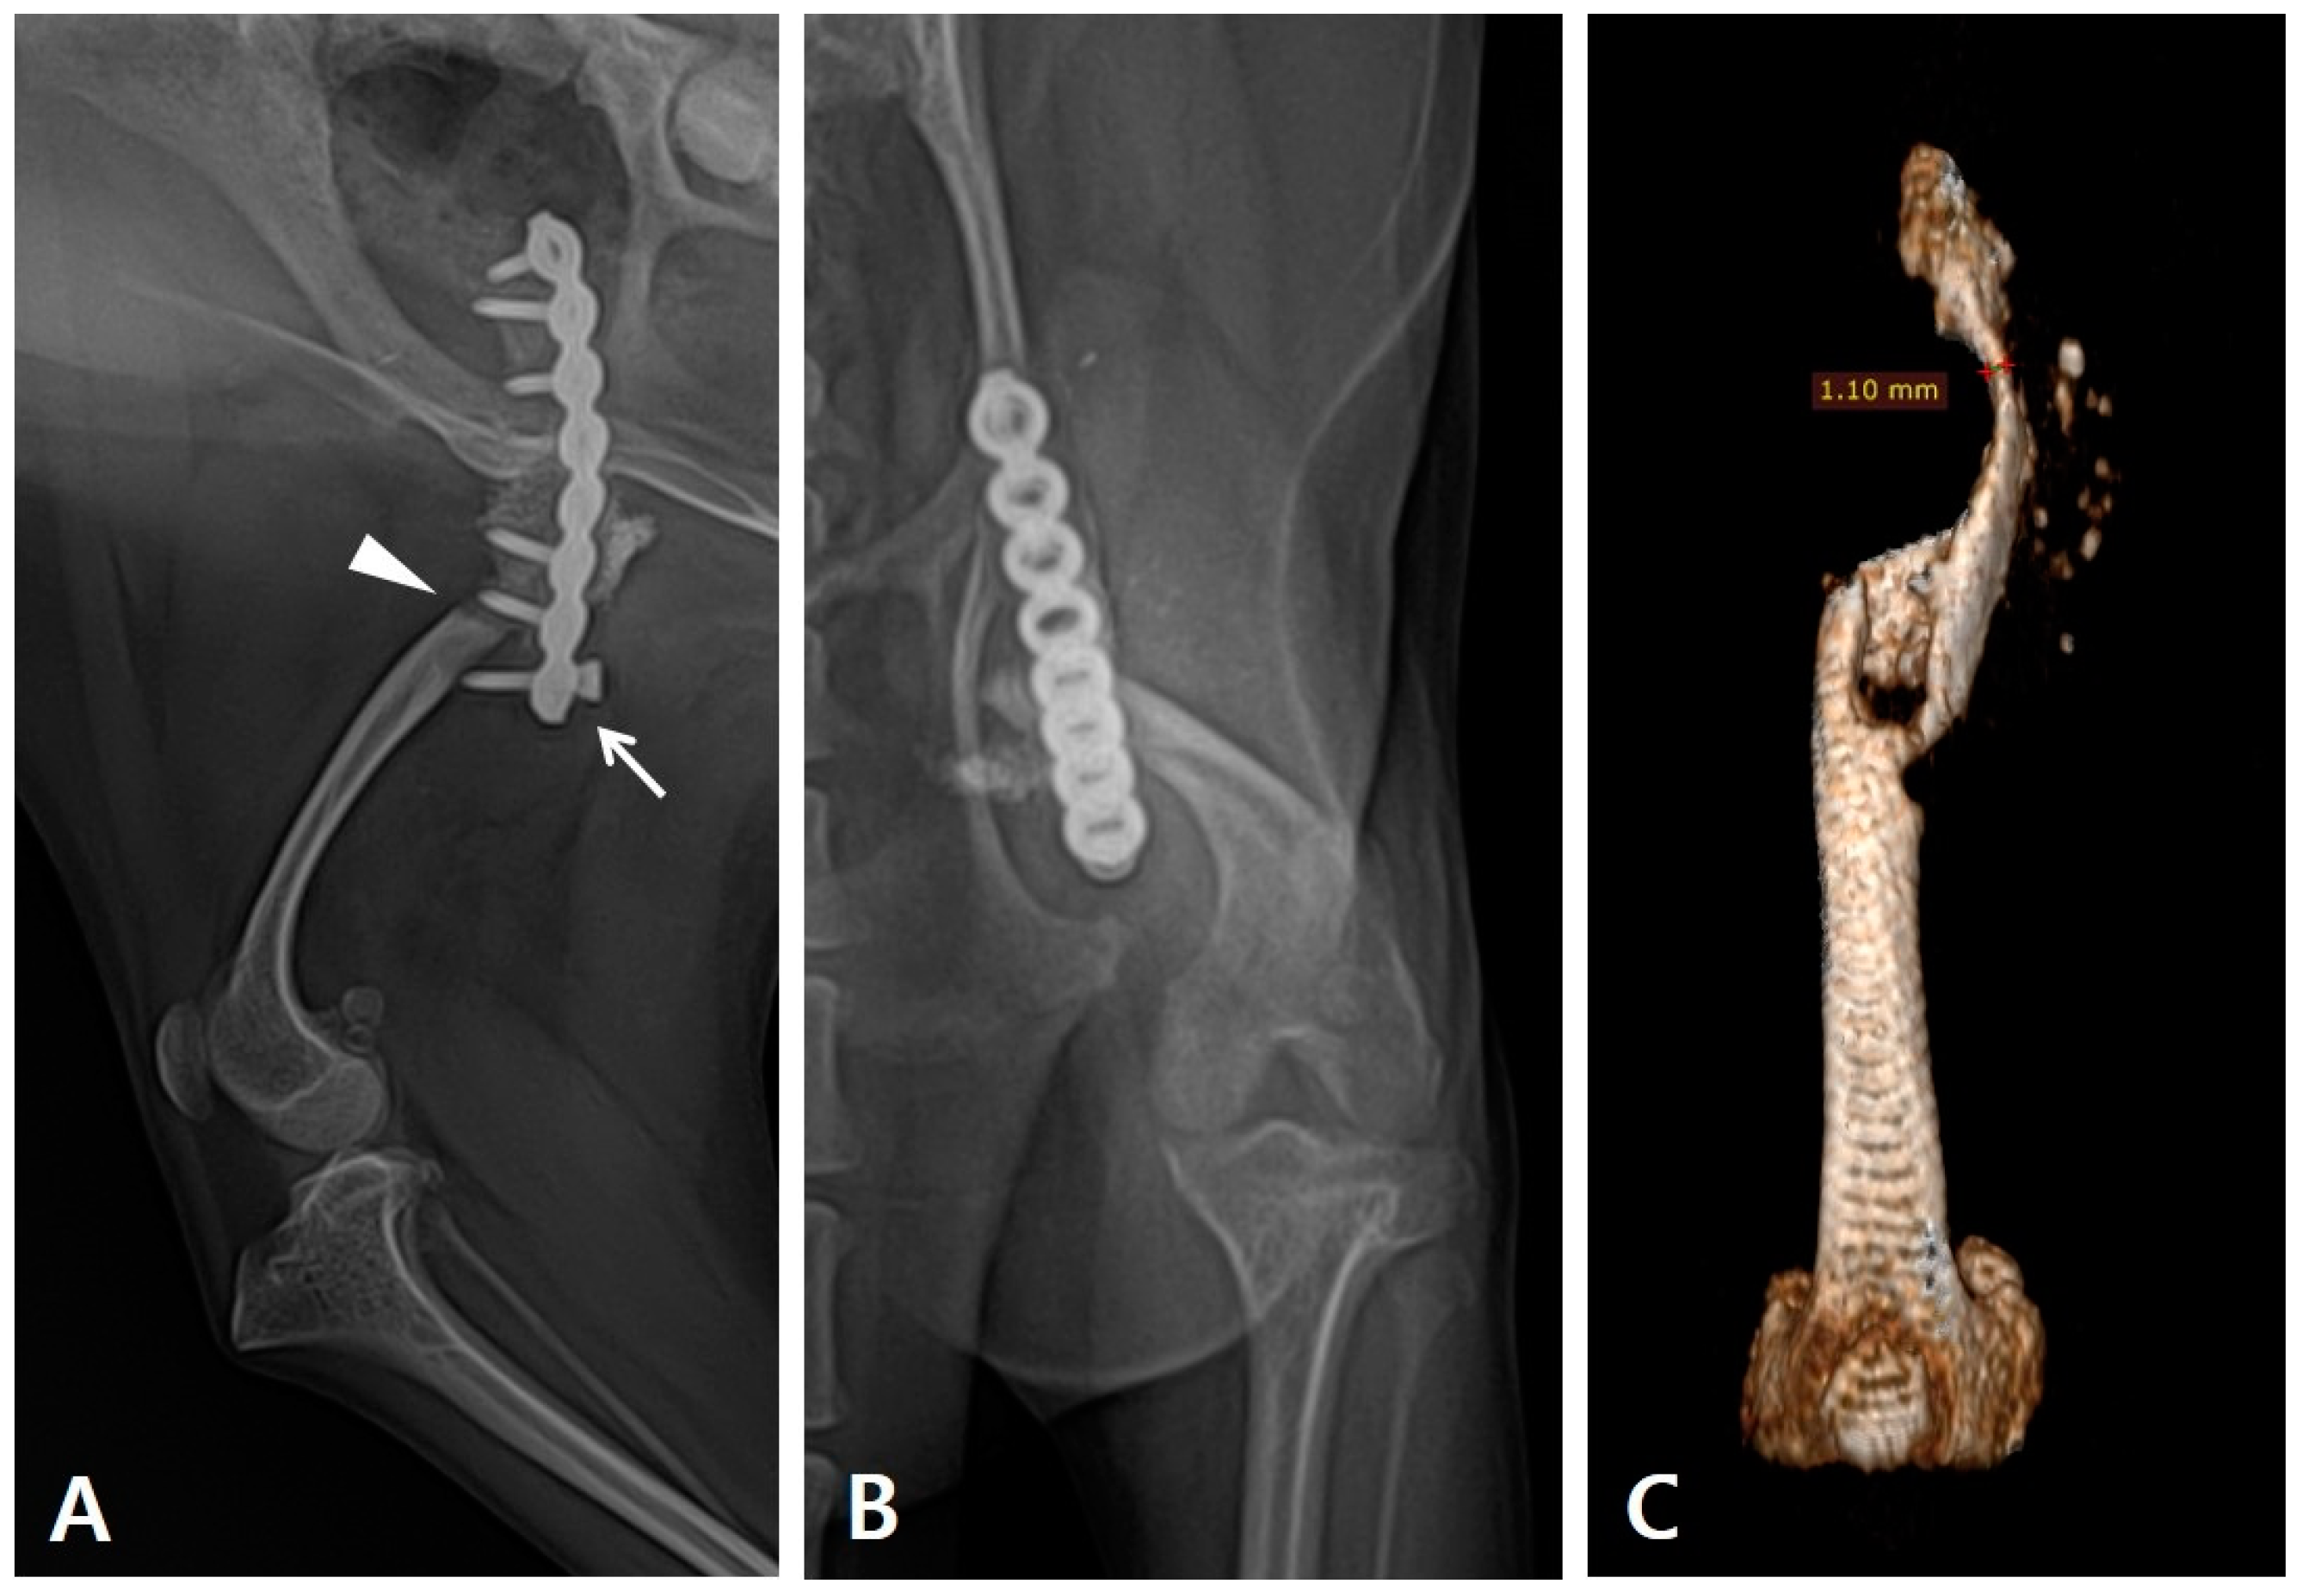

During the physical examination, the range of motion of the stifle and tarsal joints was found to be severely decreased. Radiography revealed implant failure in the left femur, severe atrophy of the proximal bone fragment, and retardation of the ipsilateral distal bone fragment of the femur and tibia compared to the contralateral side (Figure 1A,B). The failed implants were removed and computed tomography (CT) was performed for preoperative surgical planning (Figure 1C). An autogenous corticocancellous bone graft was planned and the coccygeal bone was ultimately chosen as the autograft (Figure 2).

Figure 1. Preoperative evaluation and planning carried out using radiography and CT scans. (A) Lateral and (B) craniocaudal radiograph of the patient’s left femur. Re-fracture occurred (arrowhead) with the distal-most screw pulled out (arrow). Underdeveloped femur and tibia were observed. (C) The three-dimensional reconstructed CT image of the left femur after implant removal shows severe atrophy in the proximal bone fragment, with a 1.10 mm thickness at its thinnest point.